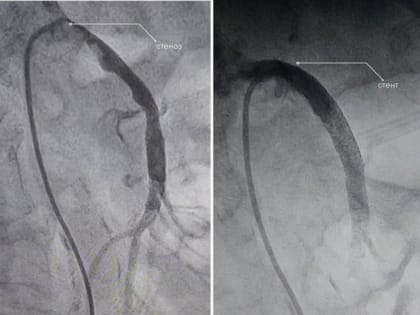

В Нижневартовске спасли женщину с редким заболеванием

Врачи окружной Нижневартовской больницы успешно провели операцию у женщины с заболеванием, которое встречается у 2-4% пациентов.

Нижневартовские врачи спасли пациентку, кровь которой перестала поступать к кишечнику

Нижневартовские врачи спасли пациентку с редким заболеванием Марина Прохорова Фото: департамент здравоохранения Югры Нижневартовские врачи спасли пациентку с редким заболеванием.